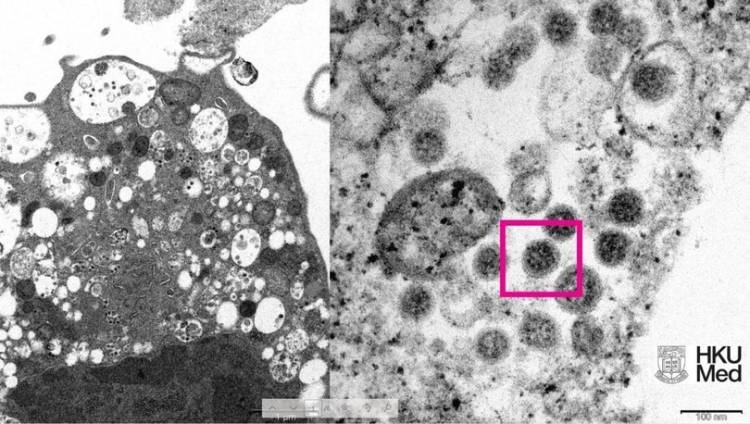

Üniversite tarafından yayınlanan fotoğrafın solunda, küçük siyah viral partiküller içeren şişmiş veziküllerle hücre hasarını gösteren, SARS-CoV-2 Omicron varyantı ile enfeksiyondan sonra bir maymun böbrek hücresinin (Vero E6) düşük büyütmeli elektron mikrografının yer aldığı ifade edildi.

Fotoğrafın sağında ise yüzeylerinde korona şekilli sivri uçlara sahip viral partikül kümelerini gösteren enfekte bir Vero E6 hücresinin yüksek büyütmeli elektron mikrografının yer aldığı belirtildi.